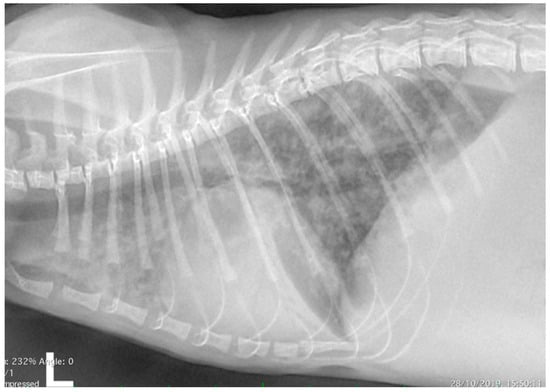

Echocardiography showed severe right atrial and ventricular dilation (Figure 2a,b) associated with right ventricular hypokinesia. Flattening of the interventricular septum was present and the internal dimension of the left ventricle was reduced. Moderate to severe tricuspid regurgitation was evident (Figure 2c) with normal morphology of the valvular leaflets. The peak velocity of the tricuspid regurgitation was 2.9 m/s. The pulmonary artery was dilated, with a pulmonary trunk to aorta ratio of 1.42. The pulmonary artery systolic flow had a proto-systolic peak (Figure 2d). Mild pericardial and pleural effusion and moderate abdominal effusion were evident. The analysis of the abdominal effusion indicated a modified transudate. All these findings were consistent with severe pre-capillary PH and R-CHF. The presence of congenital heart diseases was verified and excluded by two-dimensional and Doppler echocardiography.

Figure 2.

Echocardiography from the domestic kitten showing severe right atrial (RA) and right ventricular (RV) dilation, with reduced dimensions of the left atrium (LA) and the left ventricle (LV) (a,b). Moderate to severe tricuspid regurgitation was evident (c) with normal morphology of the valvular leaflets. The pulmonary artery systolic flow had a proto-systolic peak (d).